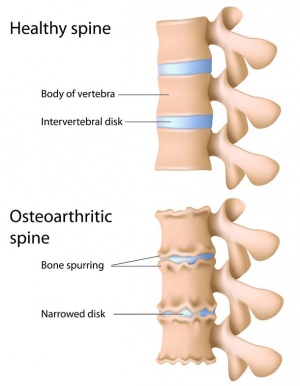

آرتروز هنگامی رخ میدهد که غضروفهایی که انتهای استخوانهای مفاصل شما را پوشش میدهند به تدریج خراب شوند. غضروف یک بافت سفت و لغزنده است که حرکت مفصلی تقریباً بدون اصطکاک را امکانپذیر میکند. در نهایت، اگر غضروف کاملاً فرسوده شود، استخوان روی استخوان ساییده میشود.

آرتروز غالباً به عنوان بیماری “سایش” شناخته میشود. اما علاوه بر تجزیه غضروف، آرتروز کل مفصل را تحت تأثیر قرار میدهد؛ باعث ایجاد تغییراتی در استخوان و تحلیل رفتن بافتهای پیوندی مفصل شده و عضله را به استخوان متصل میکند. همچنین باعث التهاب پوشش مفصلی میشود.

آرتروز ستون مهرهها

اگر کمردرد دارید، ممکن است به آرتروز ستون مهرهها مبتلا باشید. این شرایط مفاصل وجهی واقع در پایین کمر و باسن را تحت تأثیر قرار میدهد. سن و ضربه به ستون فقرات هر دو عواملی بالقوه در در این آرتروز هستند. زنان بیشتر از مردان به این بیماری مبتلا میشوند. افرادی که دارای اضافه وزن هستند یا مشاغل آنها نیاز به چمباتمه زدن و نشستن دارد نیز ممکن است در معرض خطر بیشتری باشند.

شدت علائم آرتروز نخاعی میتواند متفاوت باشد. آنها عبارتند از: